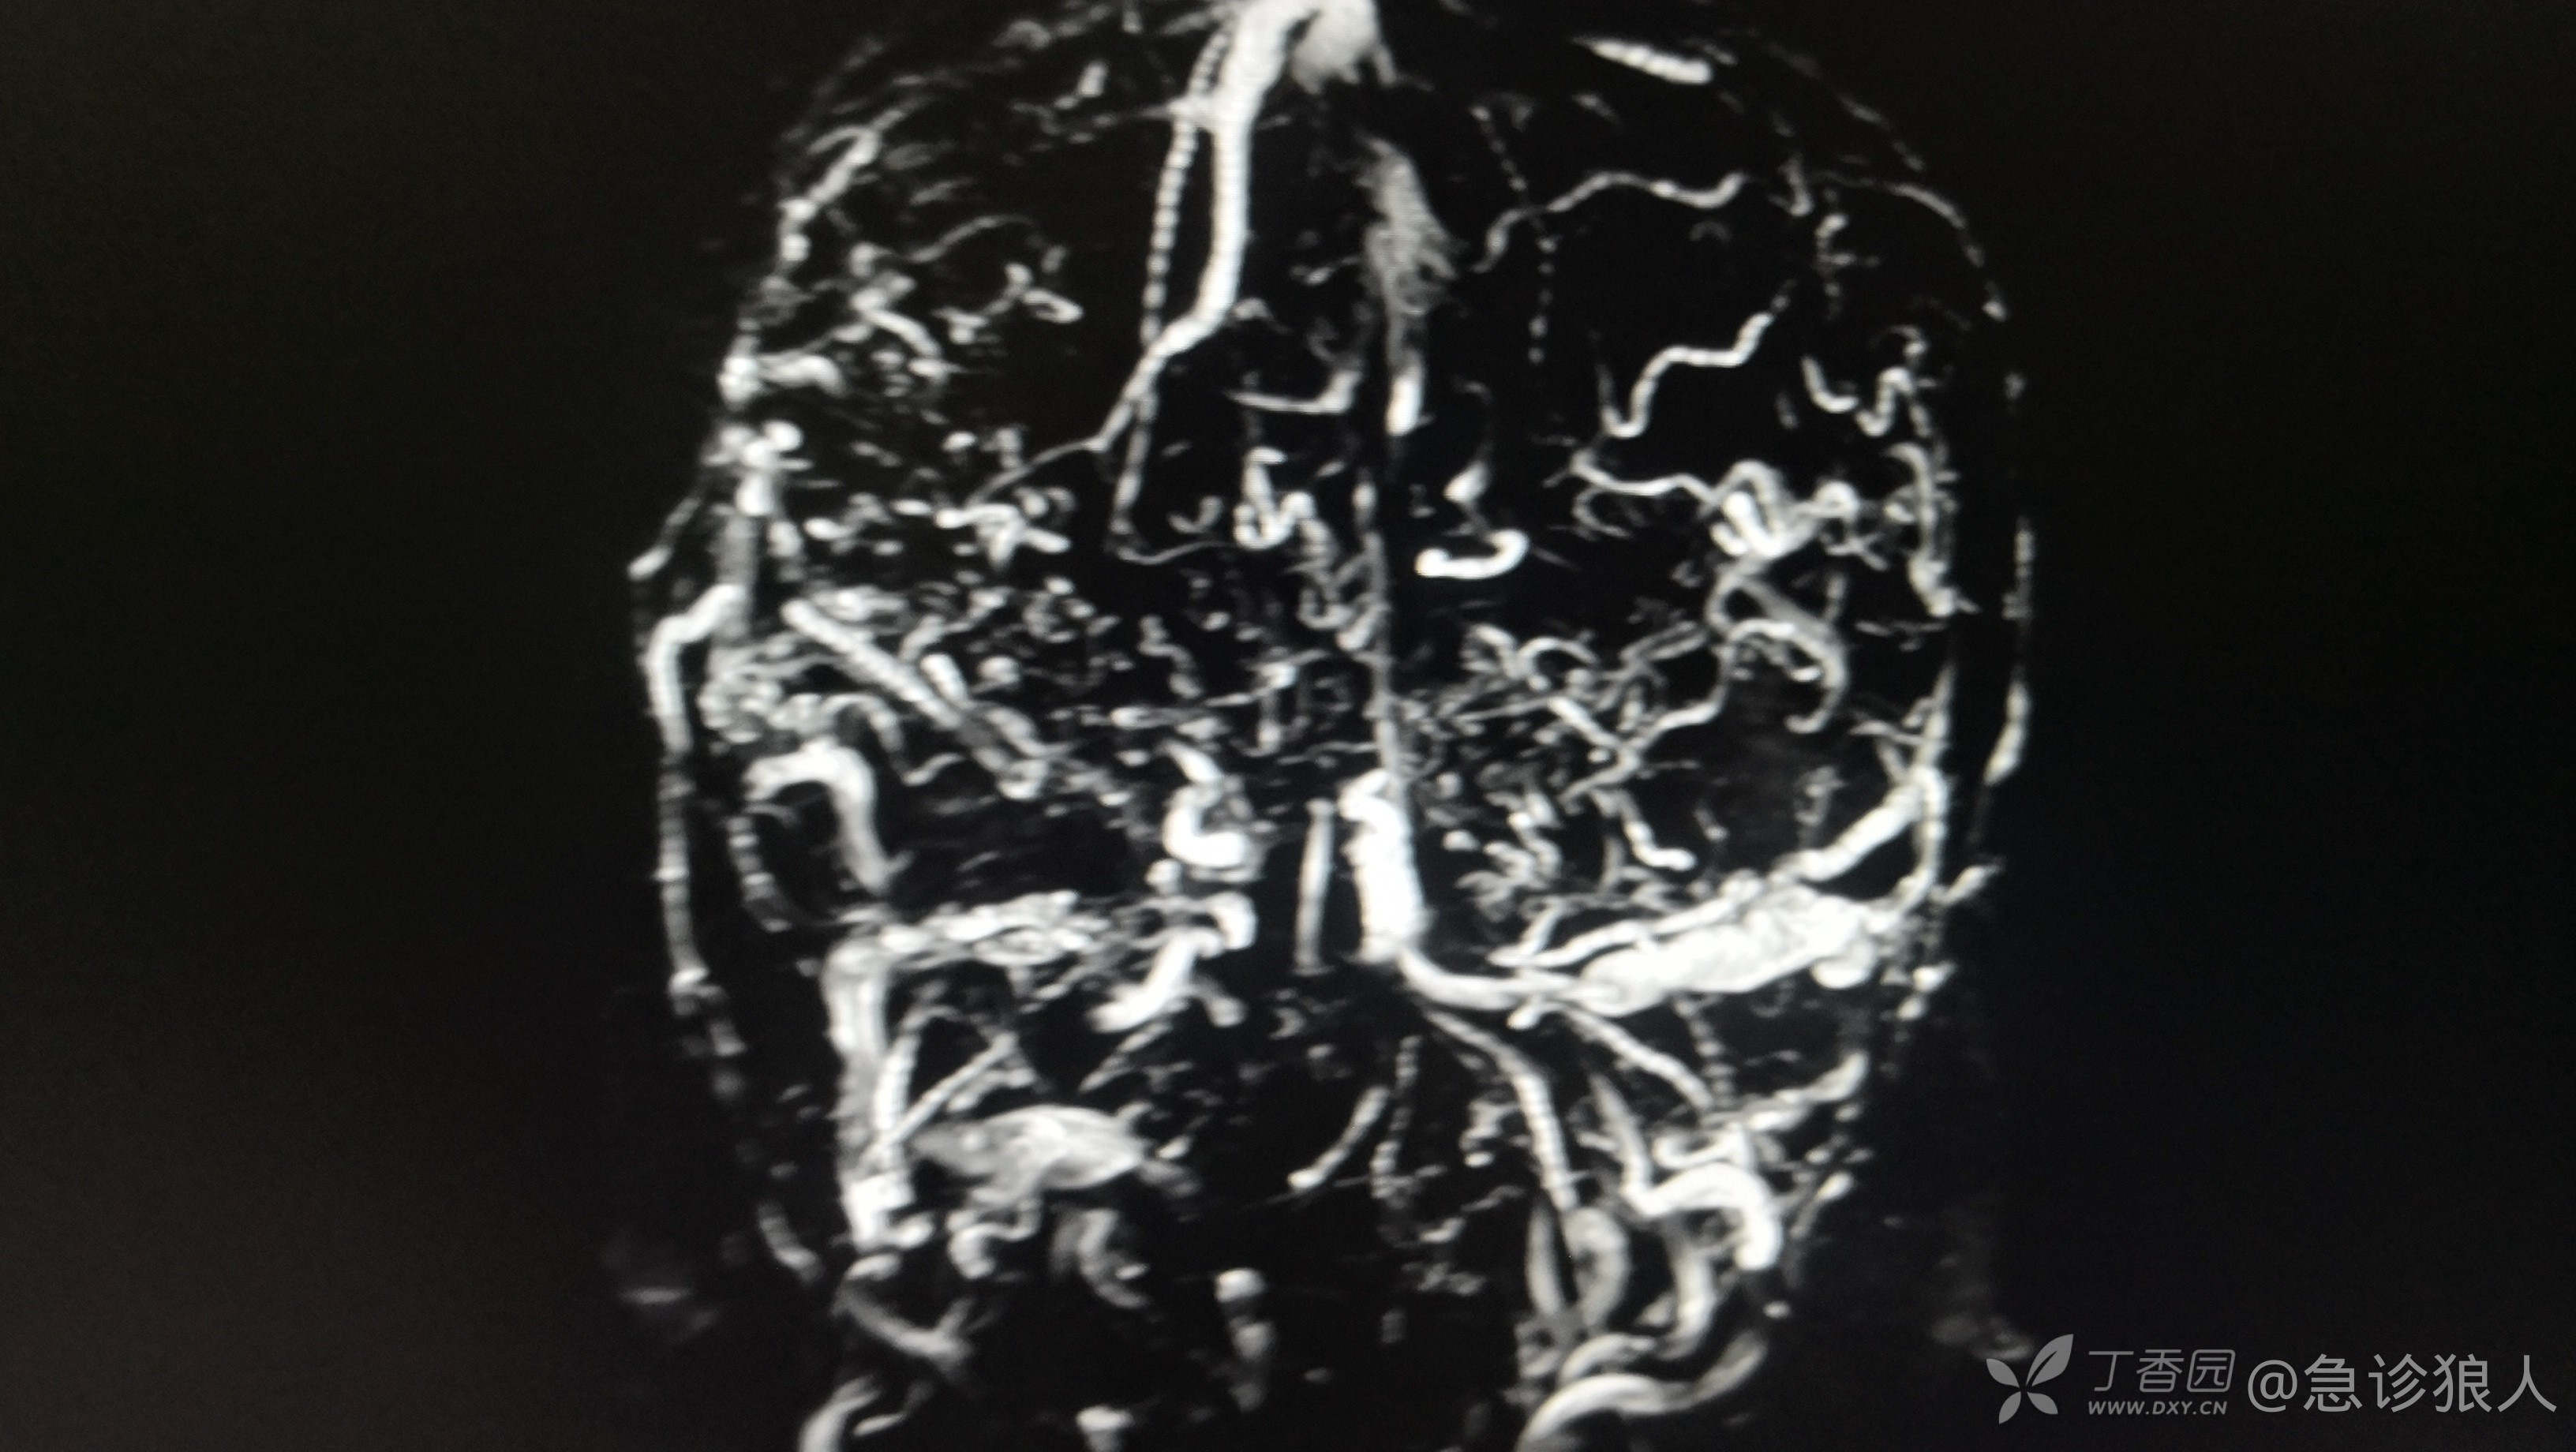

左侧大脑半球多发杂乱,迂曲血管影,与左侧乙状窦相通,考虑硬脑膜动静脉瘘可能性大。

出来结果,神内愿意收了,收上去做了DSA,动静脉瘘修补!